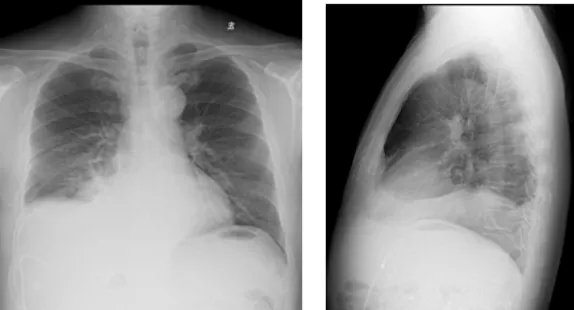

影像學(xué)檢查結(jié)果

右肺炎癥不能排除,請(qǐng)結(jié)合臨床。右側(cè)少量胸腔積液